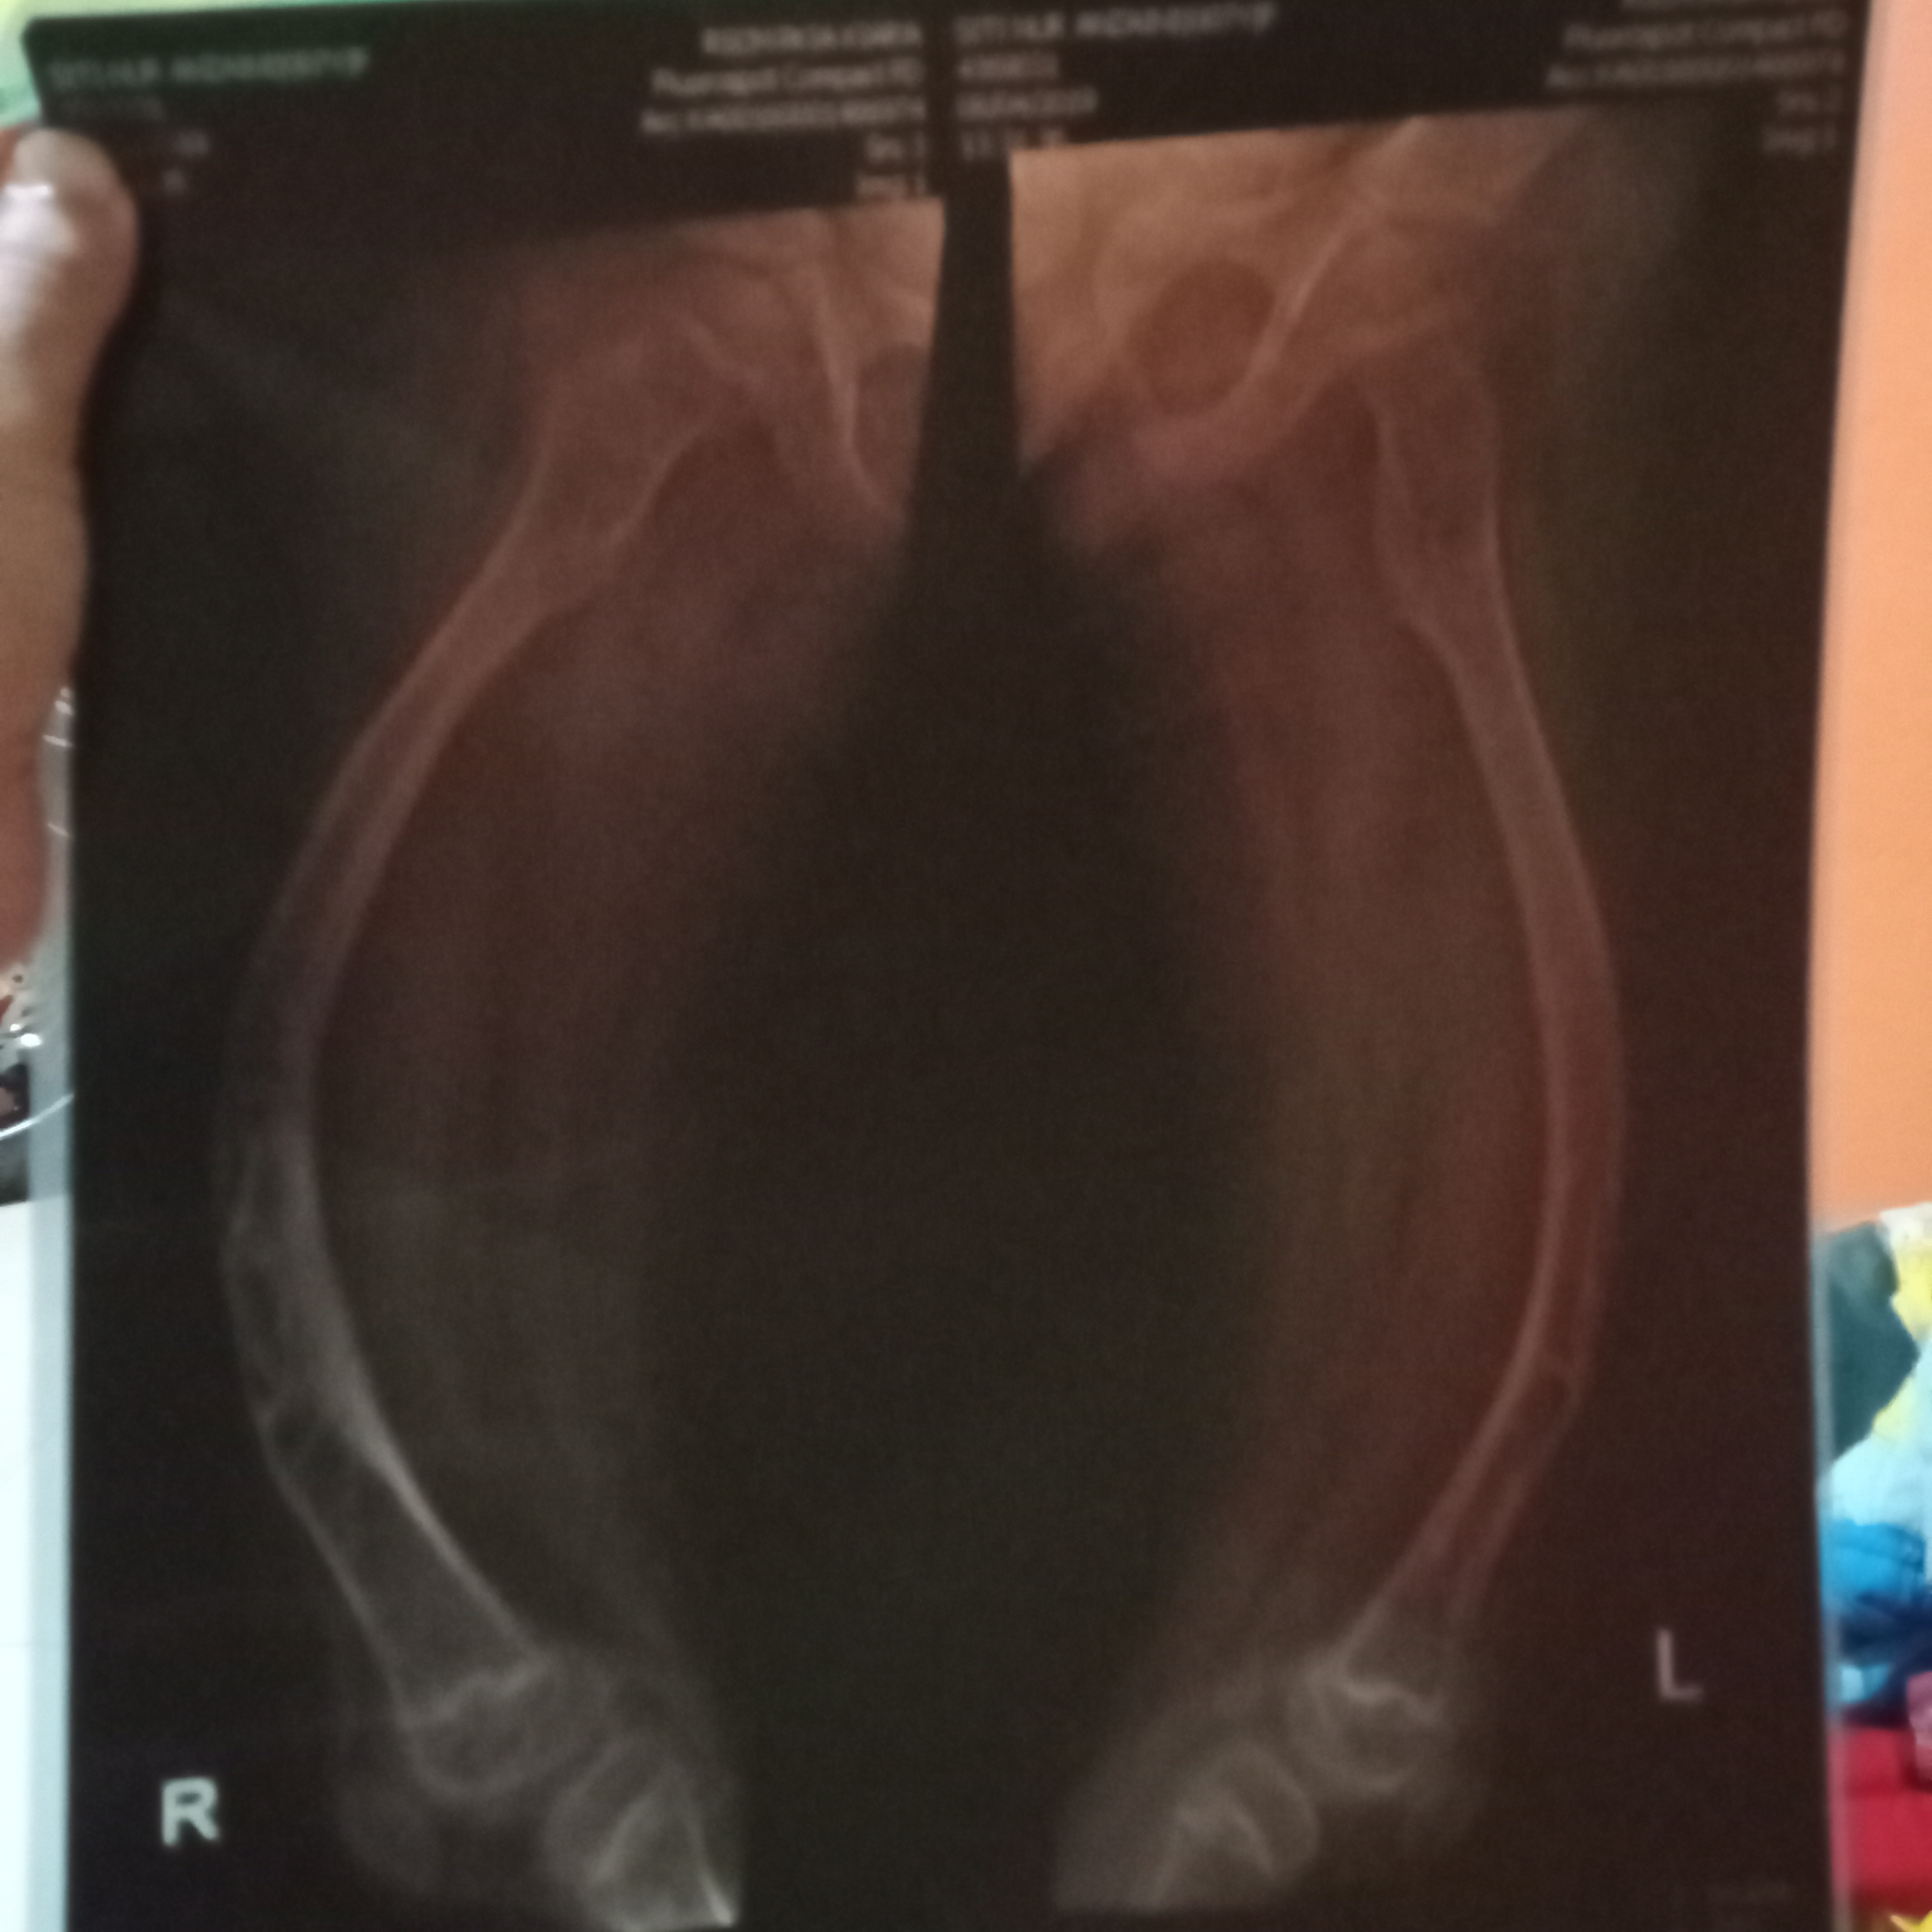

Saya pikir, setelah kejadian tersebut tidak ada hal yang serius, tetapi ternyata tidak. Anza jadi sering patah tulang bahkan kondisinya semakin buruk, kondisi kaki kiri dan kanannya menjadi bengkok.

Sebenarnya, anakku disuruh melakukan operasi pasang pen. Tapi, karena anakku tidak berani dan nangis, maka dokter memberi waktu untuk aku membujuknya agar berani untuk dioperasi. Karena, menurut tim dokter kaki kiri dan kanan anakku sudah bowing (bengkok) dan mengkhawatirkan.

Namun, kaki anza panjang sebelah dan tulang paha kanan kiri bengkok akibat patah tulang berulang kali, sehingga Anza perlu di operasi untuk perbaikan tulang agar Anza bisa berjalan normal seperti teman-temannya.